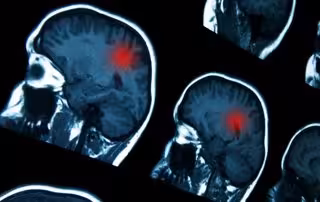

Archivo - Cerebro

Archivo - Cerebro - GOGLIK83/ ISTOCK - Archivo